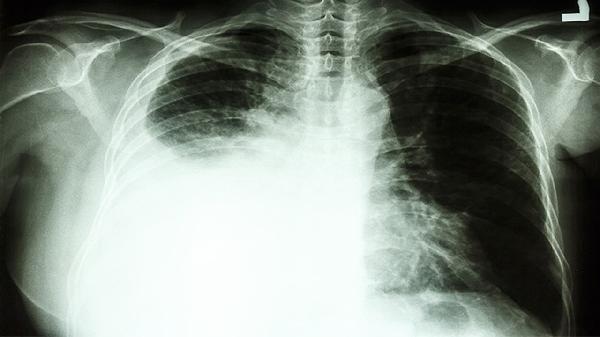

2、影像学检查要精准

X光片看骨骼,B超查肝胆,低剂量螺旋CT筛查肺部,不同部位要选对检查方式。